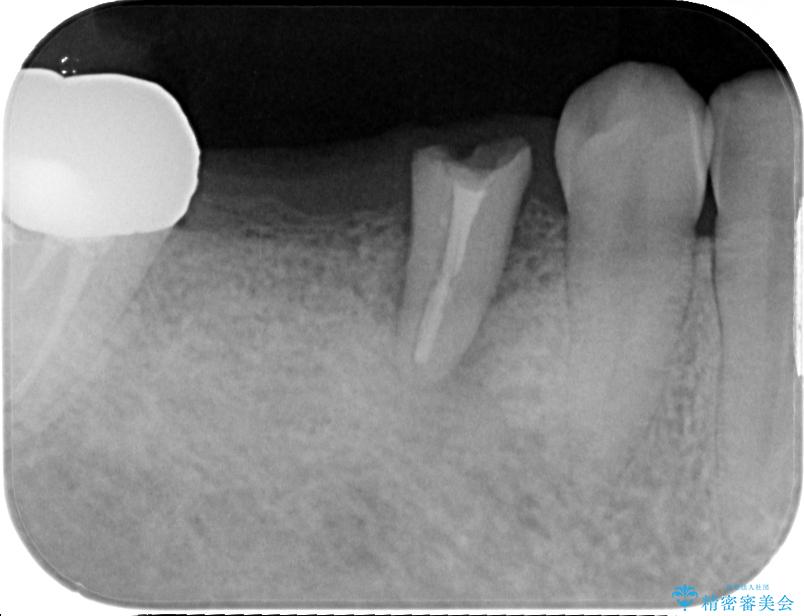

- むし歯を放置したことで、歯茎で膿が腫れ上がったしまったとのことで来院された患者様です。

ブリッジの支台歯が痛みを覚え、近医でブリッジを切断してもらって以降、そのままにしてしまったとのことでした。

問題が起きていた手前の歯から膿が出てきたことを自覚して当院を来院されましたが、既に歯根破折をしており、抜歯が必要な状態でした。

咬合力が非常に強い患者様であり、2歯欠損のブリッジ(しかも大臼歯は失活歯)は歯根破折のリスクが高すぎると判断し、抜歯部および欠損部に対して、インプラントによる補綴治療を行うこととしました。